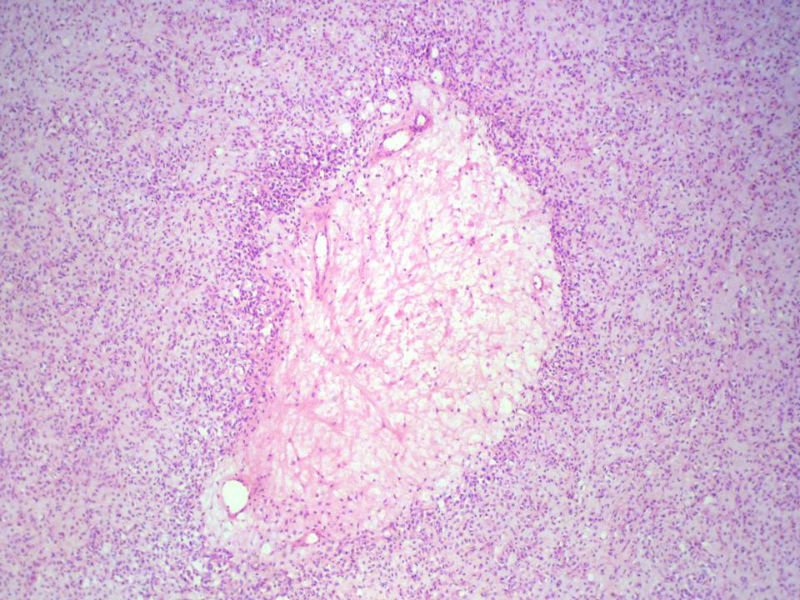

男,27岁,右股骨上段皮下肿物1年余,无明显疼痛,检查肿物明显隆起于皮下,边界清楚,手术完整切除肿物。肉眼,肿物6X6X5厘米,外观多结节状,似有包膜,切面灰白色,质韧。

特别提示:镜下核分裂3-4/HP.

3. 本例组织学改变与粘液性脂肪肉瘤,粘液样纤维肉瘤,纤维粘液样肉瘤,骨外粘液样软骨肉瘤都有重叠之处,且镜下并未见典型结构。由此,免疫组化结果就尤显重要。特别是专业书籍提到,突触素或嗜铬素阳性,对鉴别诊断有重要意义。我用CGA,也是在以上几个肿瘤中举棋不定而为。NSE和CK没用,其实我想用更多的抗体来证实更多的东西,但患者的经济条件不太好,遗憾!